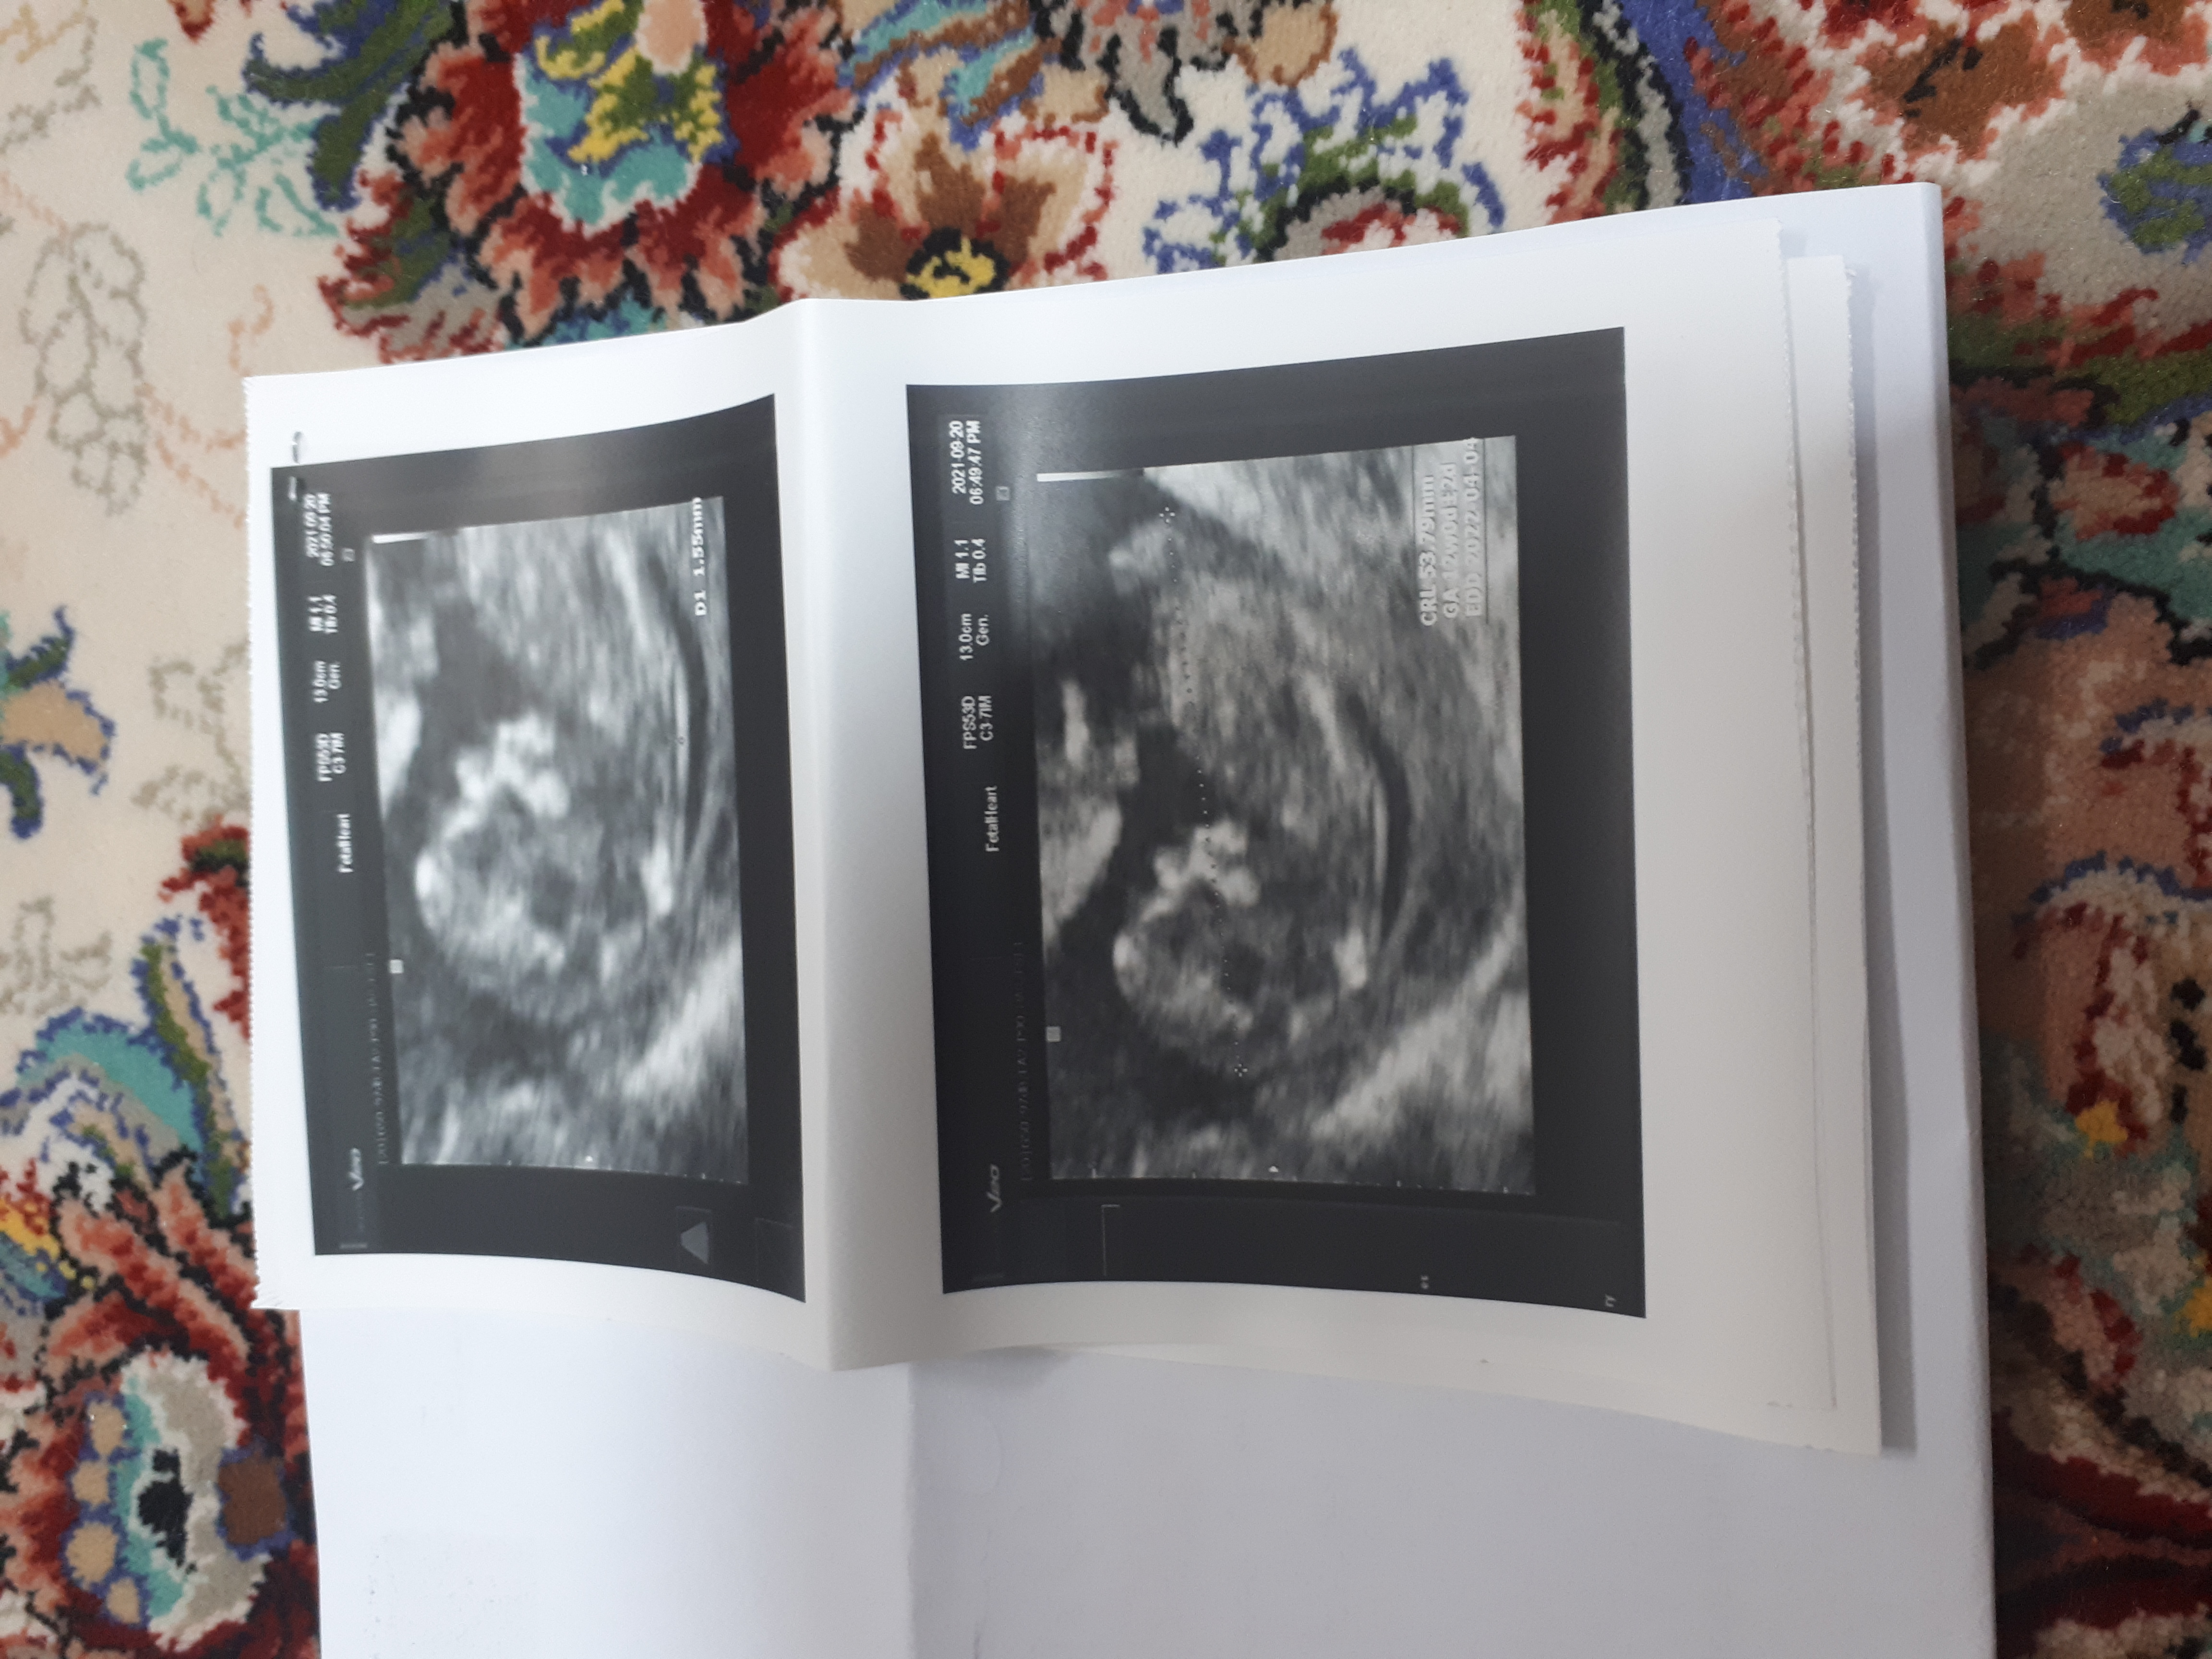

به مهارت پزشک بستگی داره برای من ان تی هر دو بار درست گفت

موافقم ب منم گفت ک ستون فقراتش ب پسر میخوره ۱۸ هفته گفتن پسره

پسره